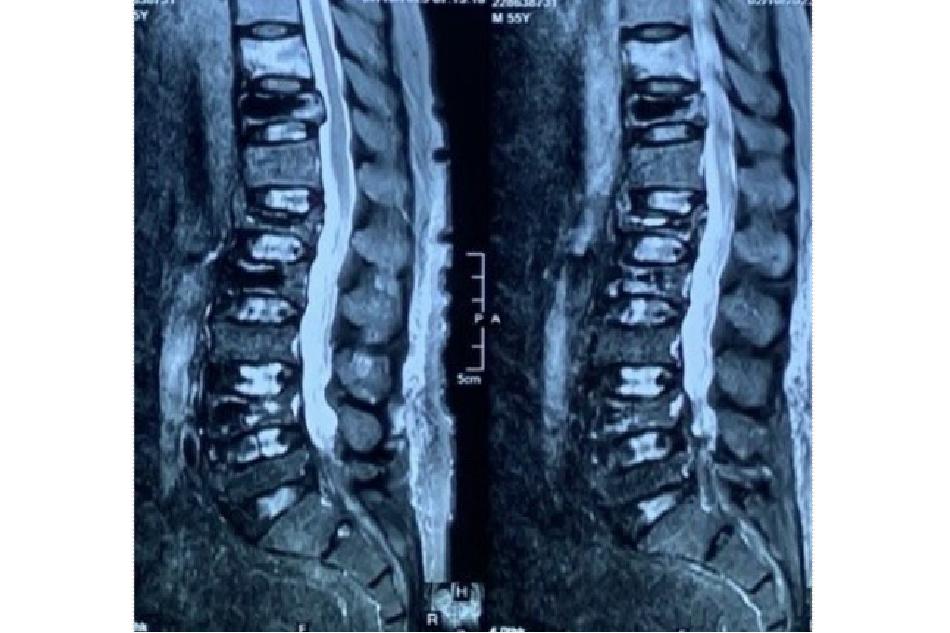

- Cộng hưởng từ cột sống: Quan trọng nhất để chẩn đoán xác định bệnh và lên phương án phẫu thuật. Có thể thấy các hình ảnh: xẹp phù nề thân đốt sống, xẹp cũ, xẹp mới thân đốt sống, ngoài ra có thể đánh giá mỏ xương thoái hóa, thoát vị đĩa đệm, thoái hóa tràn dịch diện khớp, dày dây chằng vàng hẹp lỗ liên hợp …